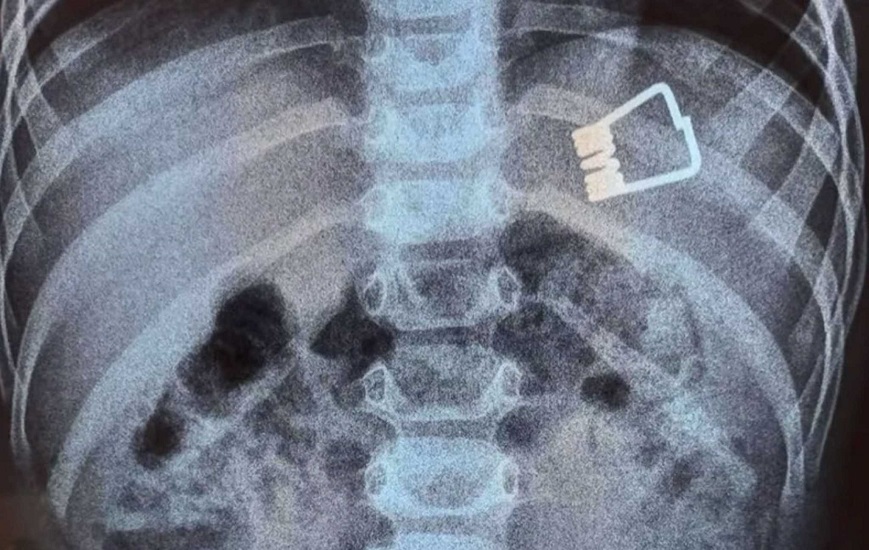

Πώς σώθηκε το παιδί που κατάπιε το μανταλάκι